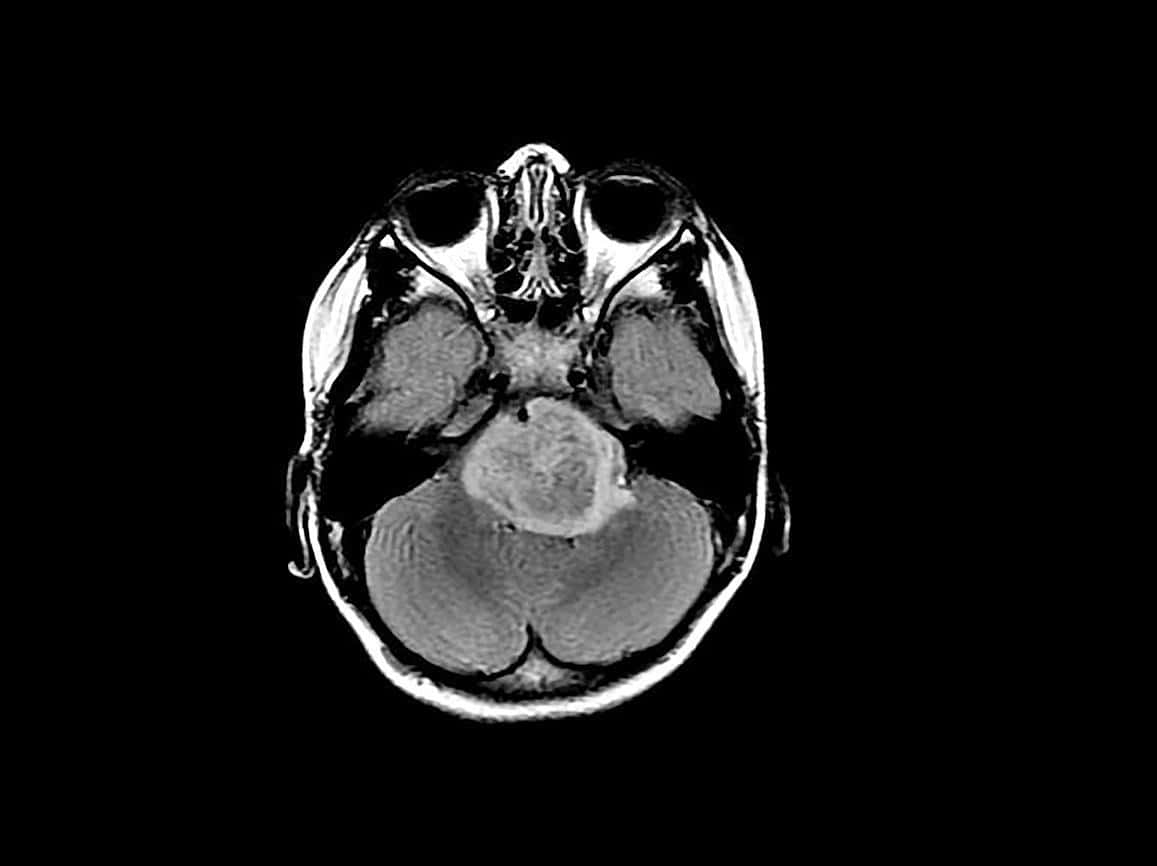

It was so hard to tell my brother that he had brain cancer. I told him to focus on getting better and he could come live with my parents soon. He lost his short term memory two days after they found the tumor, then he had brain surgery. We didn't want him to suffer telling him over and over again about his condition as he would just forget.

My parents took his ashes and kept them at home for months. She wanted to keep her promise that he would come live with them.